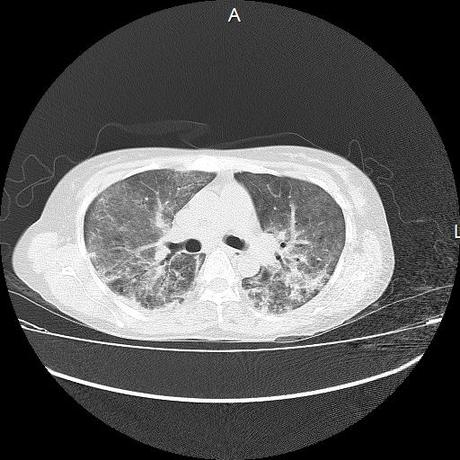

El parénquima pulmonar con areas parcheadas difusas en vidrio despulido combinadas con otras areas hipodensas de baja atenuación debidas a atrapamiento aéreo y engrosamiento intersticial y zonas de fibrosis de predominio en lóbulos medios e inferiores de ambos pulmones.

- LOS HALLAZGOS PUEDEN ESTAR EN RELACIÓN A NEUMOPATIA INTERSTICIAL PROBABLE ETIOLOGIA HIPERSENSITIVA VS AUTOINMUNE/BACTERIANA/FUNGICA.